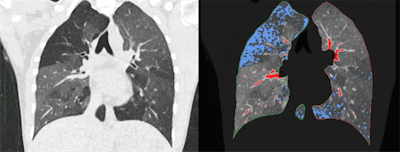

Left: Regular CT for suspected COPD. Right: Overlaid qCT. The blue areas represent the typical "air trapping" seen in COPD. The red sections only show vessels and have no pathological value. All images courtesy of Dr. Joshua Gawlitza.Software programs, which have long been helping radiologists evaluate CT images, usually assess density differences on CT scans and determine average values for the relevant regions.

This can prove very interesting in an organ like the lungs, where the qCT evaluates more than two million voxels per lobe, he added. In patients with chronic obstructive pulmonary disease (COPD), for example, the lung is not evenly ventilated. Instead there are areas where the air becomes "trapped" as the patient breathes out, and other areas that work almost normally.

"These badly ventilated areas can be identified with the qCT," Gawlitza noted.